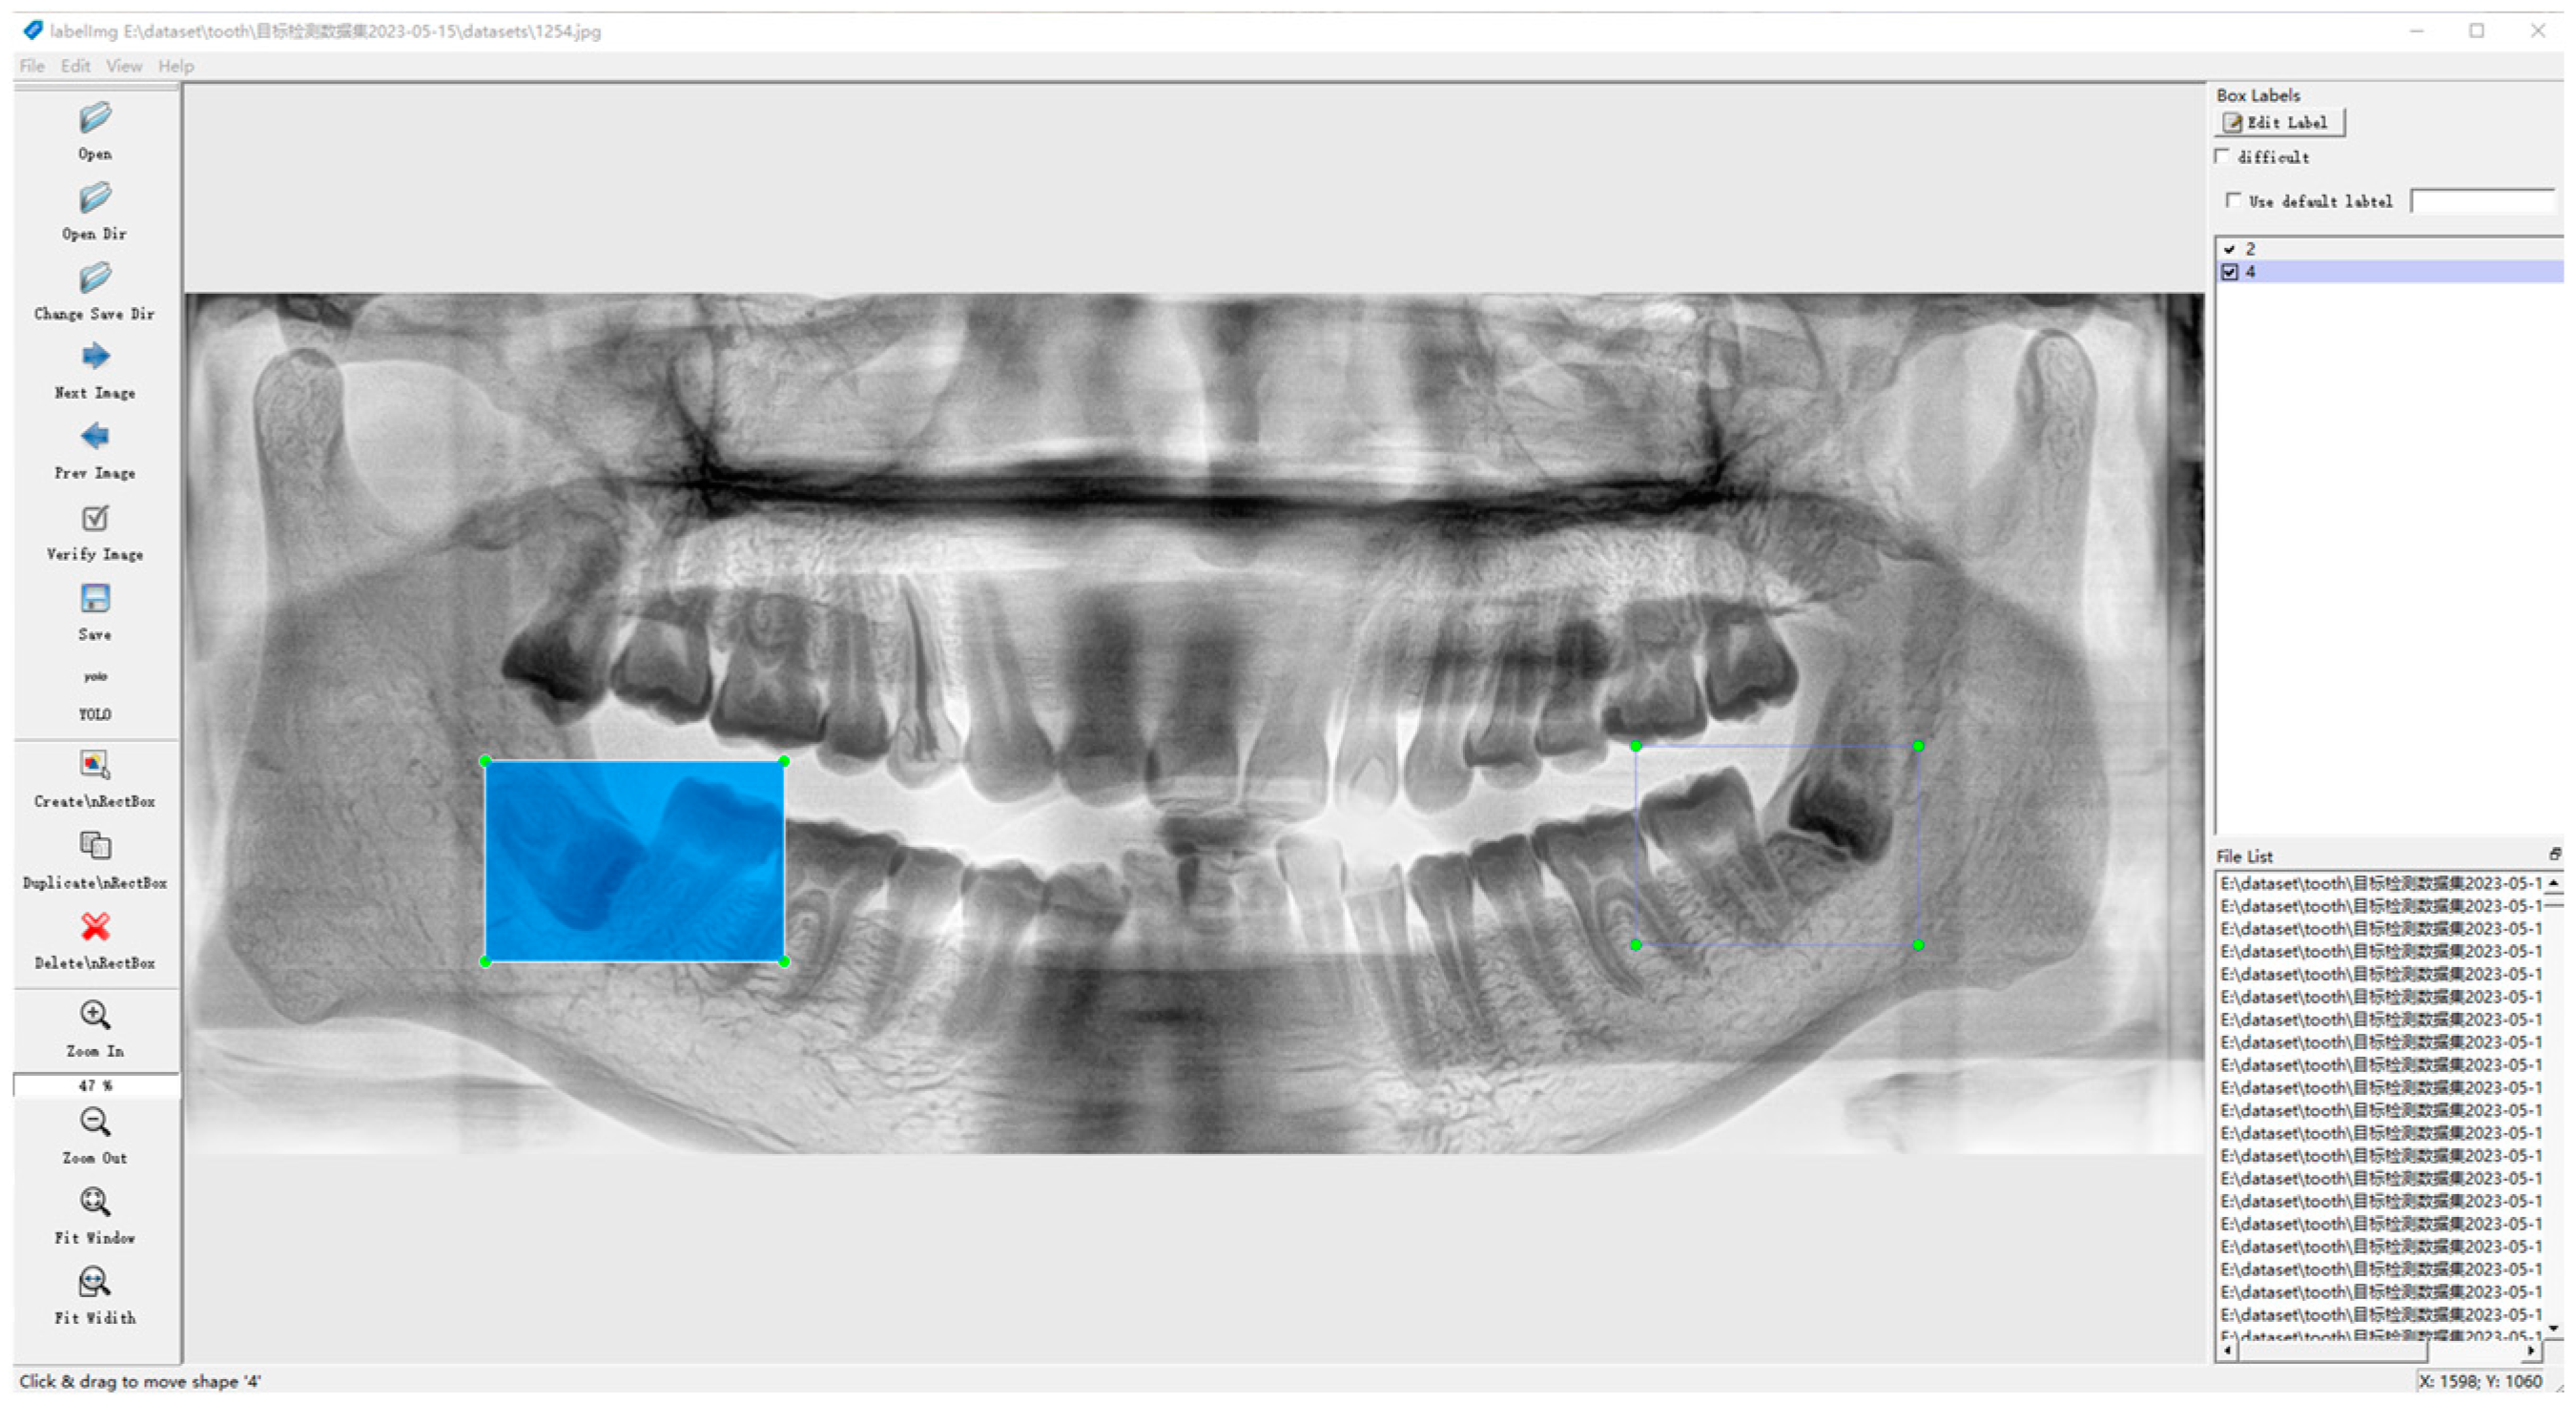

2.2.3. Data Labeling

The dataset was labeled using the open-source script LabelImg from https://github.com/HumanSignal/labelImg (accessed on 9 July 2023), a rectangular box containing both the crowns and roots of the second and third molars, as shown in Figure 4.

Figure 4. Label example diagram.